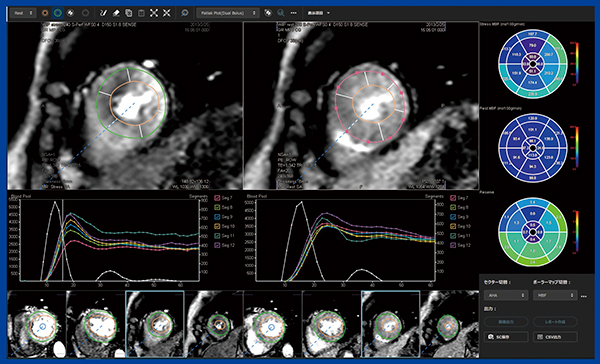

これらのアルゴリズムについては当院と藤田医科大学で共同研究を行い,その成果がREVORASに実装されている。REVORASでは,ボタン1つでDual Bolus法とSingle Bolus法による解析結果を切り替え表示でき,両者のMBFのポーラーマップを比較すると同等の結果が得られていることがわかる(図5)。

図5 Dual Bolus法(左)とSingle Bolus法(右)のMBF解析結果